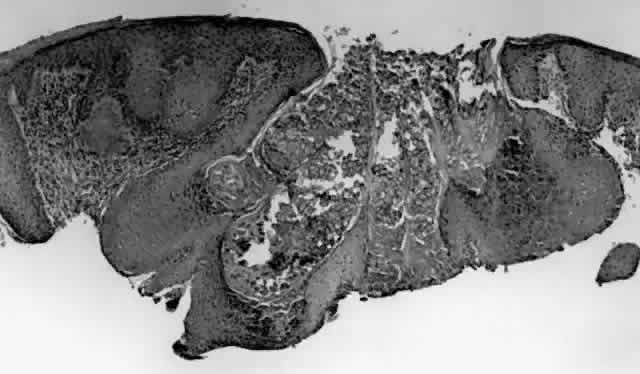

HPV-induced conjunctival squamous papillomas demonstrate papillomatosis, acanthosis, and koilocytosis (Fig. 6). Because they are mucous membrane lesions, those of the conjunctiva and lacrimal sac show no granular cell layer but will show keratinization if they are large or exposed (Fig. 7). In our experience the frequency of koilocytes is variable, even in lesions almost certain to be viral (Fig. 8). Scattered inflammatory cells may be present in the cores or epithelium. Virus can be detected immunohistochemically in the nuclei of the cells (Fig. 9).

Fig. 5. Conjunctival papilloma, histology. High-power view of acanthotic epithelium surrounding fibrovascular cores. Koilocytosis is absent. (Original magnification × 200)

Squamous papillomas of the eyelid are exophytic lesions with multiple fronds, each showing acanthotic epithelium around a fibrovascular core. There is typically hyperkeratosis and koilocytosis. Inflammatory cells may be present.